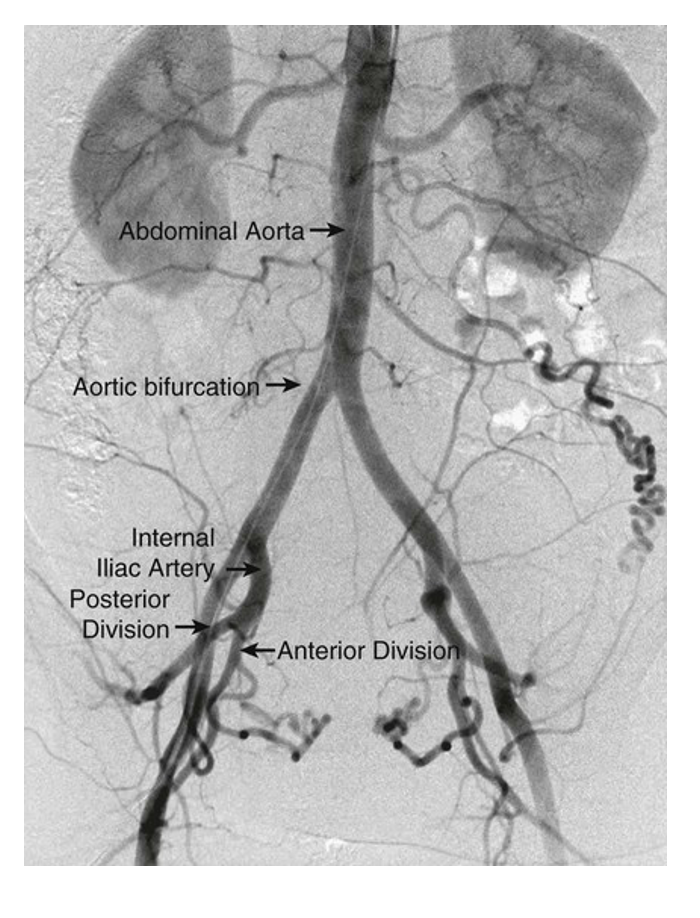

Complete the blanks & what imaging modality is this?

Female pelvic arteriogram